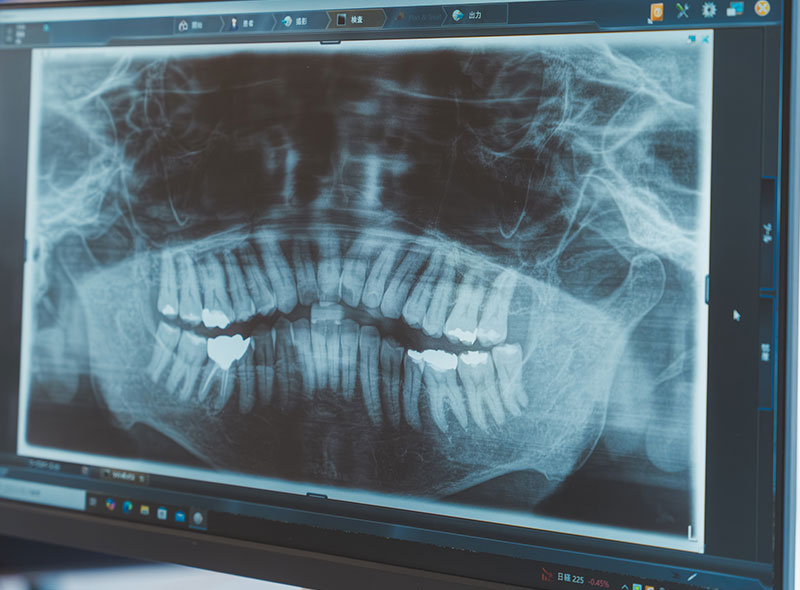

CT撮影による正確な診断

インプラントは骨の厚みや形状に合わせて埋入位置を決定するため、精度の高い画像情報が不可欠です。当院では、インプラント治療を行う多くの方に歯科用CT撮影を実施し、骨の状態を3次元的に把握しています。従来の平面的なレントゲンよりも詳細な情報を得られるため、リスクの早期発見につながり、より精度の高い治療計画の立案が可能です。